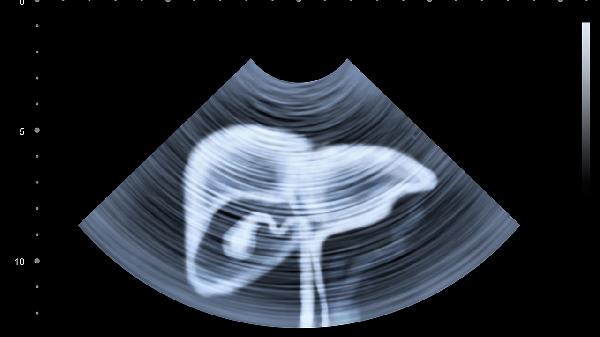

对于转氨酶轻度升高且无其他异常表现的患者,通常优先选择血液检查、超声或弹性成像等无创手段。通过肝功能复查、病毒性肝炎筛查、自身免疫抗体检测等项目,可明确常见病因如乙肝、丙肝、酒精性肝病等。若发现脂肪肝或药物性肝损伤,可通过调整生活方式或停用可疑药物观察指标变化。这类患者多数无需立即进行肝穿刺,但需定期监测转氨酶水平。

当转氨酶持续异常超过半年,或伴随黄疸、肝区疼痛、凝血功能异常等警示症状时,需考虑肝穿刺。该检查对诊断不明原因肝纤维化、早期肝硬化、遗传代谢性肝病等有重要价值。特殊人群如免疫抑制患者出现转氨酶波动,或影像学发现肝脏占位性病变时,穿刺活检有助于鉴别肿瘤或特殊感染。但需注意凝血功能障碍、大量腹水等情况属于穿刺禁忌。